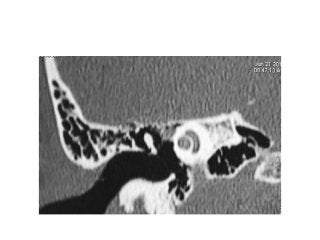

Temporal bone CT. Look at the sub-cochlear canaliculus or sub-cochlear

tunnel that can allow endoscopic transcanal retrocochlear access to the IAC

and drain the petrous apex cells